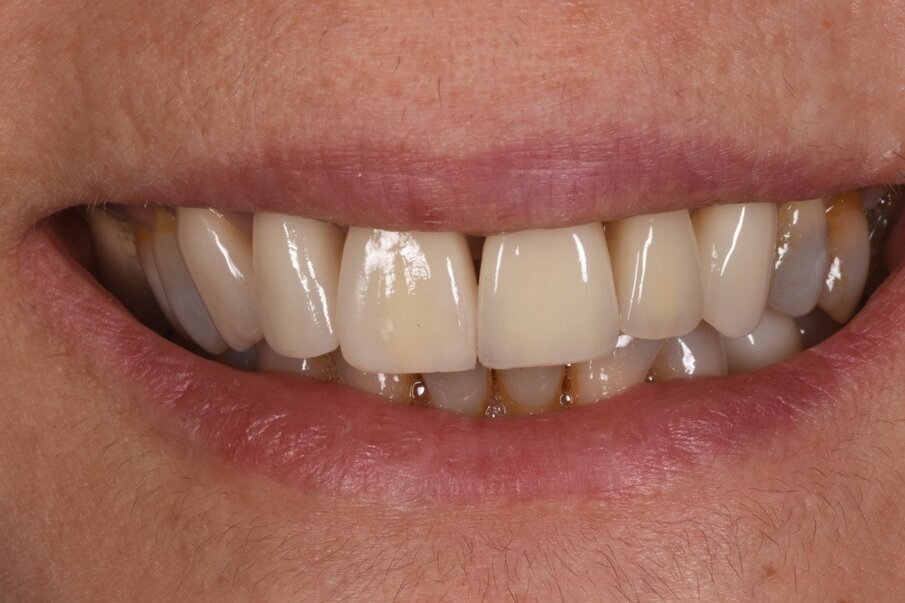

Nell’autunno 2009 una paziente di sesso femminile e di 37 anni si era riferita presso il nostro studio per migliorare il proprio sorriso (Fig. 1). All’epoca la paziente venne trattata con un DSD (Digital Smile Design) che prevedeva un allungamento di corona clinica sugli incisivi superiori, l’inserzione di un impianto nel sito 22, una GBR e innesto di connettivo per migliorare il profilo emergente del dente stesso e la riabilitazione con corone singole (Figg. 2, 3).

Le radiografie del caso completato nell’inizio del 2010 (Fig. 4) evidenziano la precisione del lavoro che è poi stato mantenuto nel corso degli anni. L’incisivo centrale destro 11 era stato trattato con apicectomia in passato ed era l’unico dente non vitale della riabilitazione. La paziente era seguita dal protesista che aveva portato a termine il caso. Nel 2021 la signora si è ripresentata con sintomatologia sul dente 21. Il lavoro eseguito nel 2010 era ancora in buone condizioni fatta eccezione per 11-12 ove 12 presentava una recessione gengivale con esposizione del collarino della cappetta galvanica che supportava la corona in ceramica e 11 presentava una piccola fistola nella sua porzione vestibolo distale (Figg. 5-7). La diagnosi era abbastanza semplice, l’11 aveva una frattura verticale e una prognosi infausta.